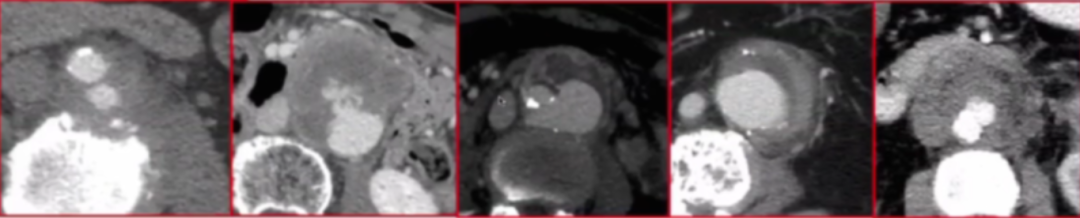

该研究(2005年9月-2024年5月)共纳入175例感染性主动脉瘤患者(男性142,女性33例),平均年龄64.8岁。这些患者患病部位为胸主动脉31例、内脏分支受累26例、胸腹联合5例、腹主动脉113例。

临床表现主动脉周围炎症97%、瘤体渗漏76%,部分患者合并椎体侵蚀、腔静脉血栓。

案例1:74岁男性患者,术前及6年瘤体的影像对比显示,动脉瘤瘤囊实现完全消退,体现出腔内治疗后长期的积极效果。

Complete aneurysm sac regression

案例2:42岁HIV阳性男性患者,术前与术后术后随访14年多的影像表明,动脉瘤瘤囊也完全消退,说明即使患者存在HIV感染这一特殊情况,腔内治疗仍能取得良好的长期预后。

案例3:75岁男性沙门氏菌感染导致的感染性主动脉弓瘤,采用“颈动脉-颈动脉搭桥、颈动脉-左锁骨下动脉搭桥+TEVAR(胸主动脉腔内修复术)+无名动脉烟囱技术”的治疗方案。术前及术后至6年半的随访结果显示,动脉瘤得到有效控制,患者长期预后良好。

案例4:45岁女性,胸、腹主动脉同时感染,术前与术后9.5年影像对比可见,经过治疗动脉瘤情况得到显著改善,长期随访显示治疗效果稳定,瘤体得到有效控制。